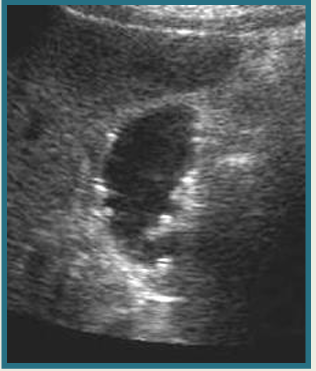

term image

mucocele